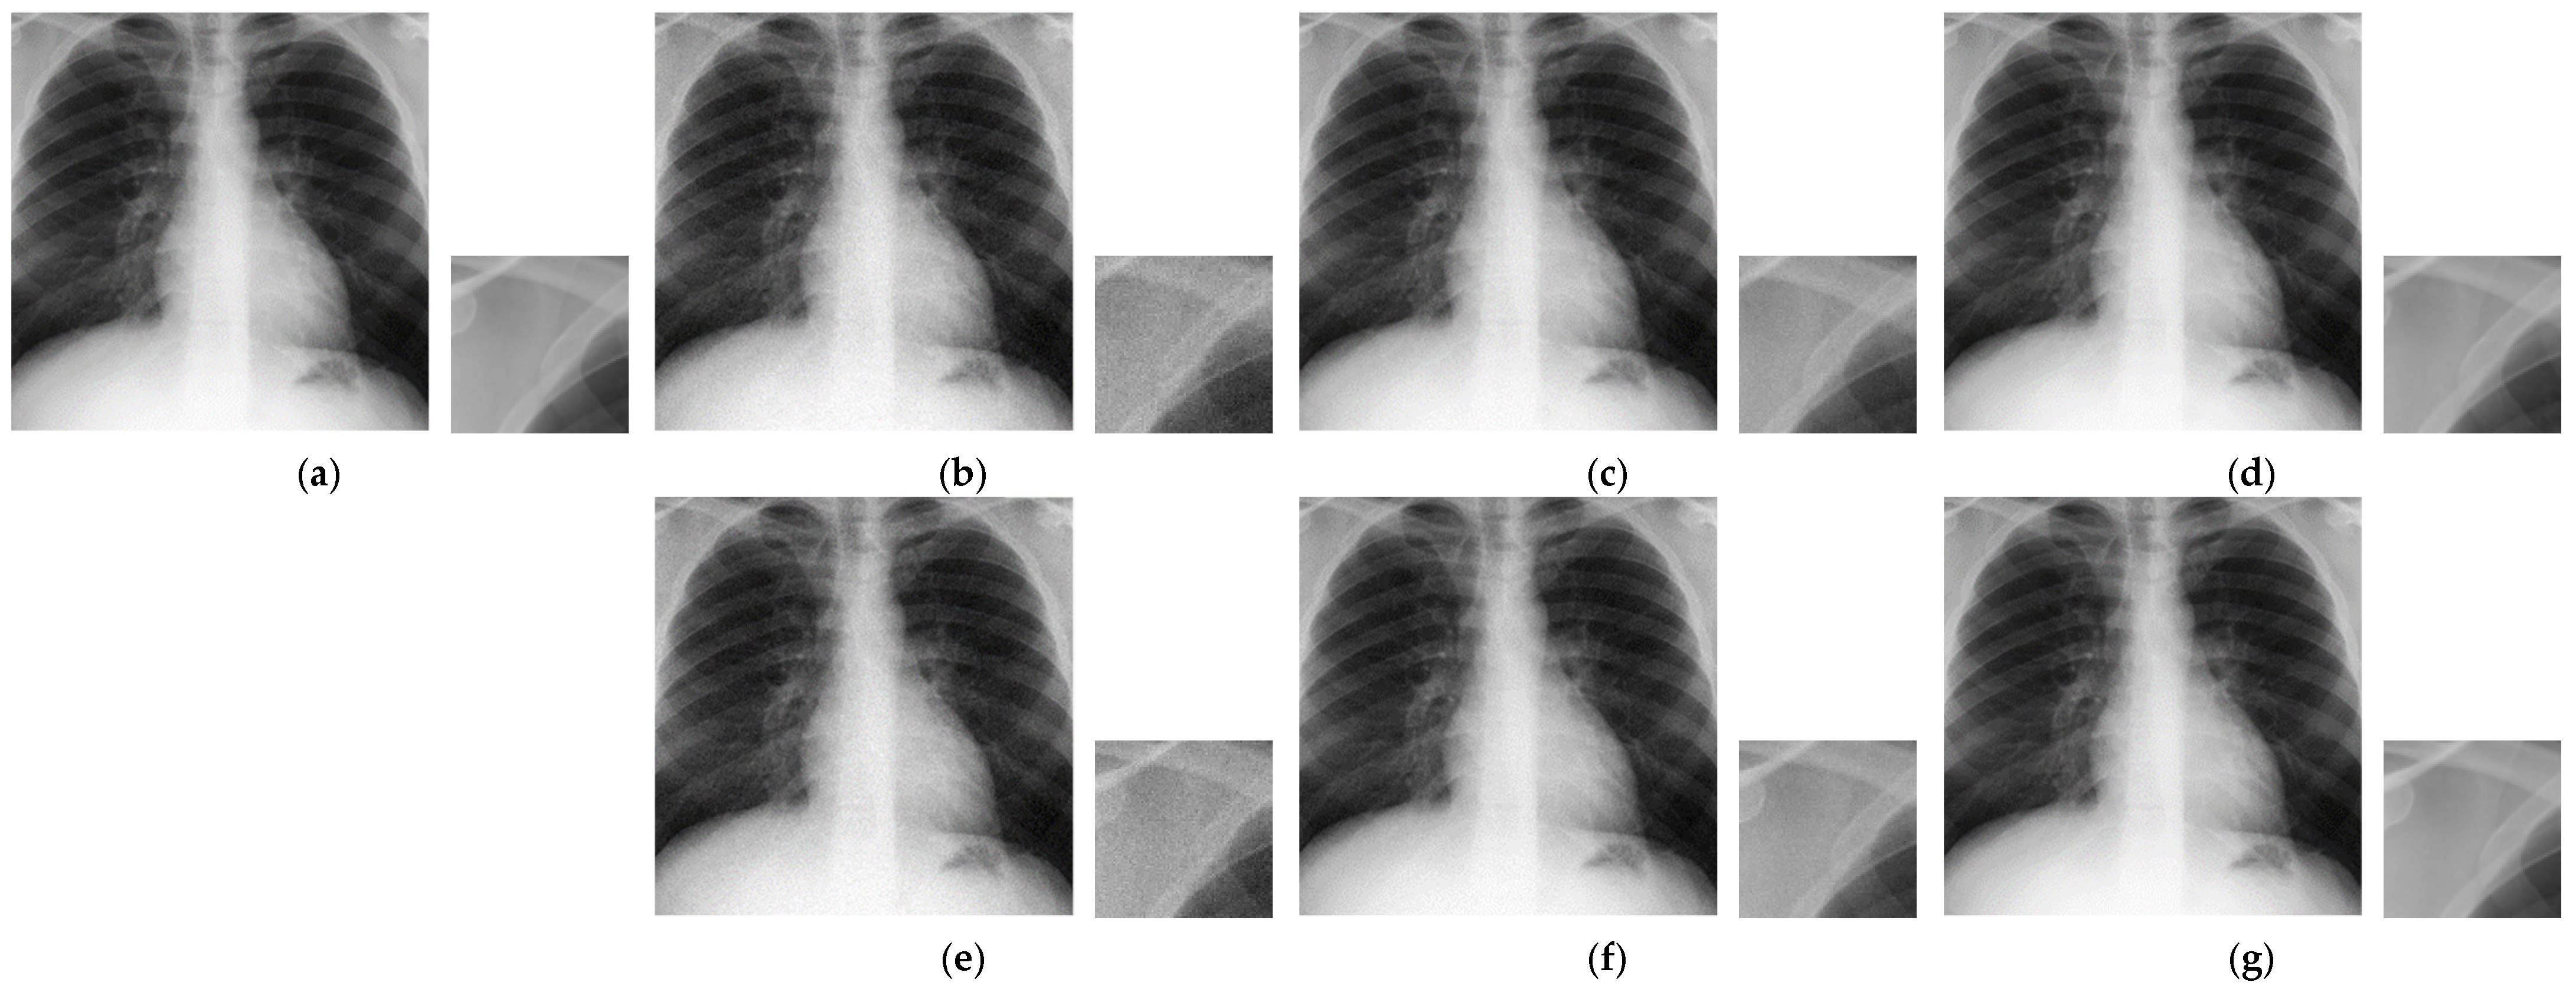

4.3.2. Proposed Data Augmentation

Figure 7.

Example images of the proposed noise-based augmentation method. (a) is original image. (b–d) are conventional method decoded noisy images. (e–g) are proposed method decoded noisy images. The JPEG quality factor is set to (80, 90, 100) from left to right. The top left corners are zoomed in every image and are shown beside them.